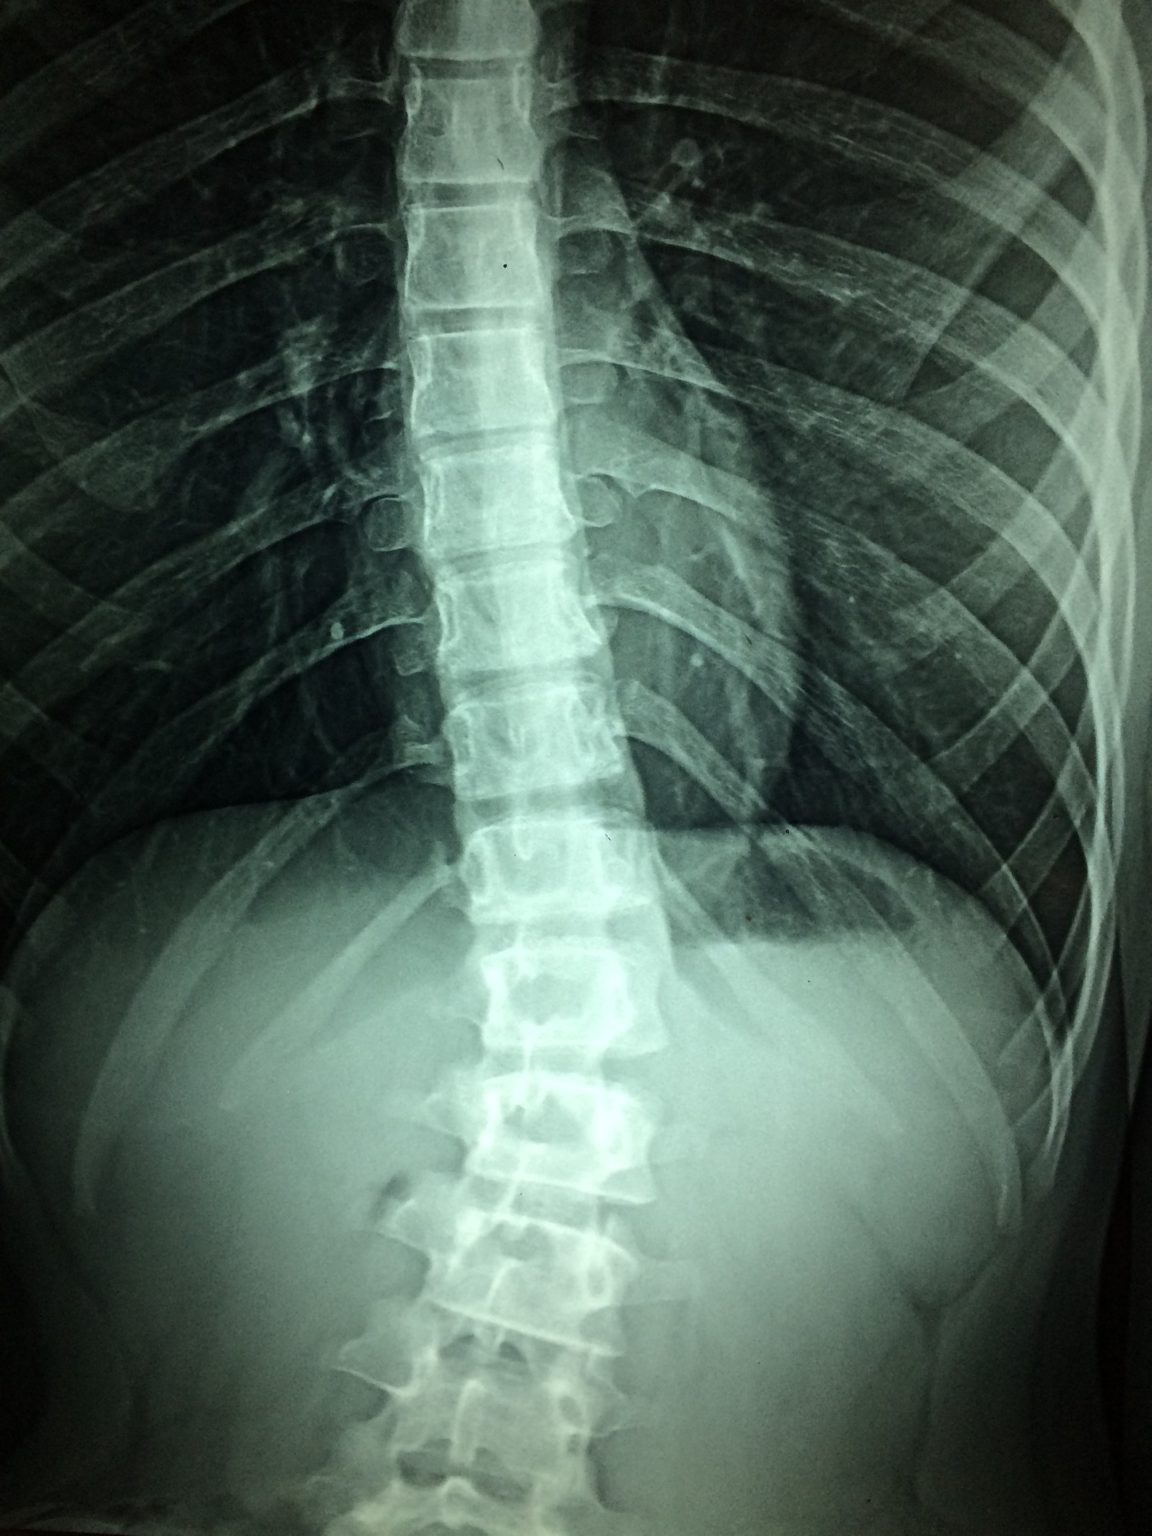

From www.alamy.com

doctor examining patients Spine xray and MRI scans. Diagnosis of How Are Back Injuries Diagnosed Doctors use many tools to help figure out the possible cause for your back pain, which. Find out what’s causing your back pain and what the. diagnosis of back pain. Doctors use various tools to help diagnose the possible cause for your back pain, which helps. back pain can range from a muscle aching to a shooting, burning. How Are Back Injuries Diagnosed.